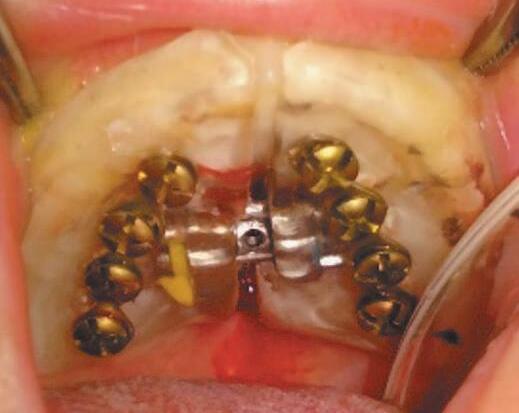

Descrição Técnica

1. Moldagem da arcada superior do neonato realizada com silicone de condensação (Perfil, Vigodent, RJ) e moldeiras de acrílico perfuradas e customizadas. O modelo de gesso (tipo III, Asfer, SP) é isolado com Cel-Lac (SS White, RJ), e sobre ele é confeccionado um dispositivo em acrílico, contendo um parafuso expansor (Morelli Orthodontics, SP) e duas placas de osteossíntese (titânio, 1,5 mm) fixadas lateralmente ao parafuso expansor (Fig. 1-5).

Fig. 1-5. dispositivo em acrílico contendo um parafuso expansor (Morelli orthodontics, sP) e duas placas de osteossíntese (titânio, 1,5 mm) com quatro furos e parafusos expansores de 6,5 a 9 mm, fixadas lateralmente ao parafuso expansor.

2. O posicionamento das placas de osteossíntese no aparelho é planejado com base na TC, prevendo a fixação no palato na projeção da parede medial da maxila, com angulação precisa para evitar danos aos germes dentários. São utilizadas placas com quatro furos e parafusos expansores de 6,5 a 9 mm, dependendo da amplitude de expansão necessária.

3. A instalação do dispositivo é realizada sob anestesia geral, intubação orotraqueal fixada à esquerda para cirurgiões destros e à direita para canhotos. O paciente é posicionado em decúbito dorsal, com hiperextensão cervical.

4. Os miniparafusos de 16 mm são inseridos no palato perpendicularmente, na projeção planejada (Fig. 1-6).